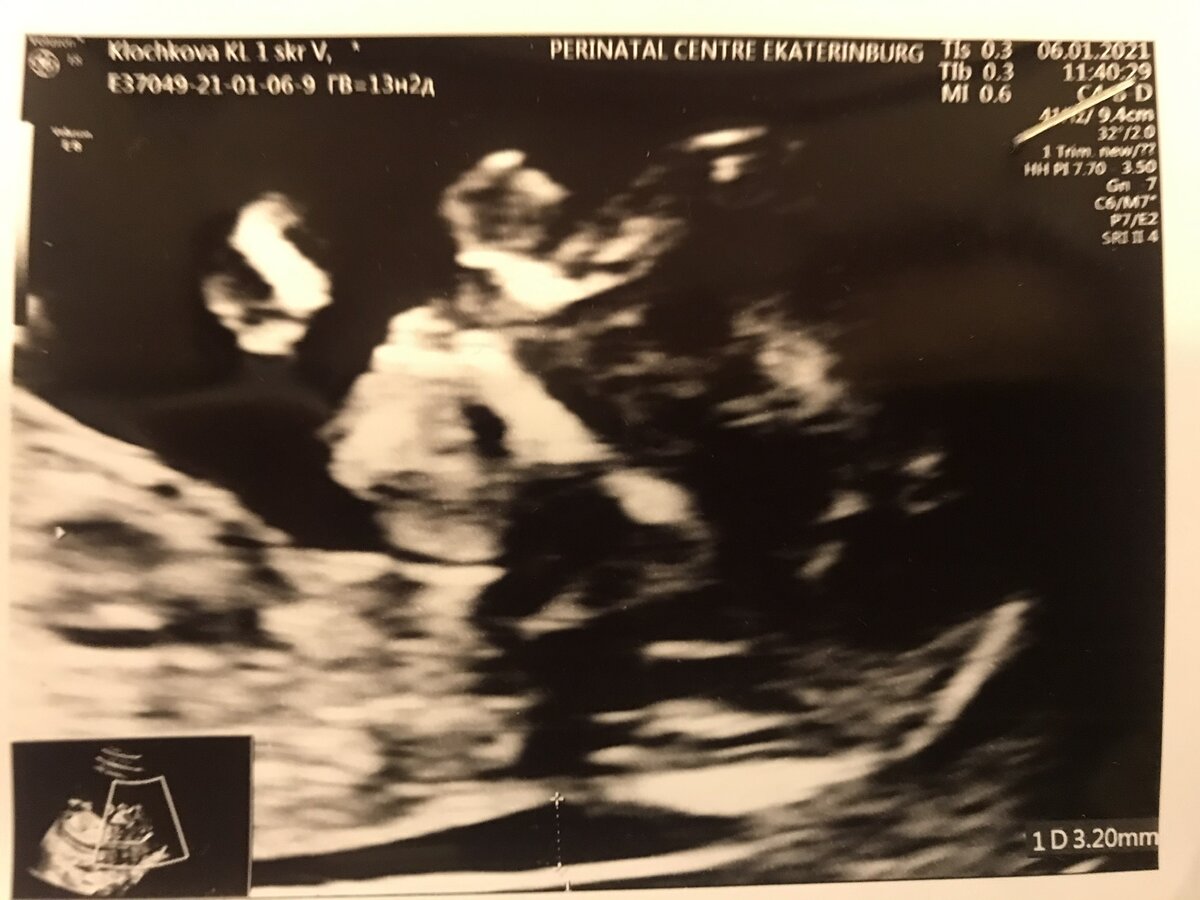

Фото автора, видно то самое увеличенное ТВП.

И вот я уже расслабилась и просто наслаждалась изображением малютки, как выяснилось, что у плода значение ТВП выше нормы. Сказали, что это один из маркеров хромосомной аномалии и нужно сделать дополнительное исследование. Сказали, что скорее всего всё в порядке, но нужно поехать в другую больницу на экспертное УЗИ и там же сдать кровь. Тут же выписали направление на сегодня и отправили.

По пути я, конечно, полезла в интернет искать, что это за зверь такой - ТВП. Оказалось, что аббревиатура обозначает толщину воротникового пространства. У плода на ранних сроках есть небольшая полость по задней поверхности шеи, заполненная жидкостью. Она исчезает к концу первого триместра, поэтому важно сделать узи до начала 14 недели, чтобы оценить её размеры. При синдроме Дауна и некоторых патологиях сердца в воротниковом пространстве скапливается больше жидкости и по её количеству можно предположить наличие нарушений у малыша. Я прочитала, что это далеко не главный показатель наличия заболевания, необходимо сдать анализ крови и только после этого делать выводы. Часто увеличение ТВП встречается и у здоровых детей, так что я надеялась, что у меня всё в порядке. К тому же основной анатомический критерий синдрома Дауна - размер носовой косточки - был в пределах нормы.

Я приехала на место, клиника удивила уровнем сервиса, необычного для государственного учреждения. Позже я узнала, что сюда направляют беременных с осложнениями и выраженными факторами риска (возрастных, с соматическими заболеваниями, с выявленными пороками развития плода). В больнице был свежий ремонт, в регистратуре встретила милая девушка-администратор и буквально за ручку проводила на анализ крови. Он должен был быть готов уже через час-полтора, пока же меня так же за ручку проводили на УЗИ. Там отметили, что в целом плод развивается нормально и тоже зафиксировали увеличенный размер ТВП. Видимо оборудование здесь получше - изображение было более качественным, я ещё раз с восторгом полюбовалась на свою кроху.